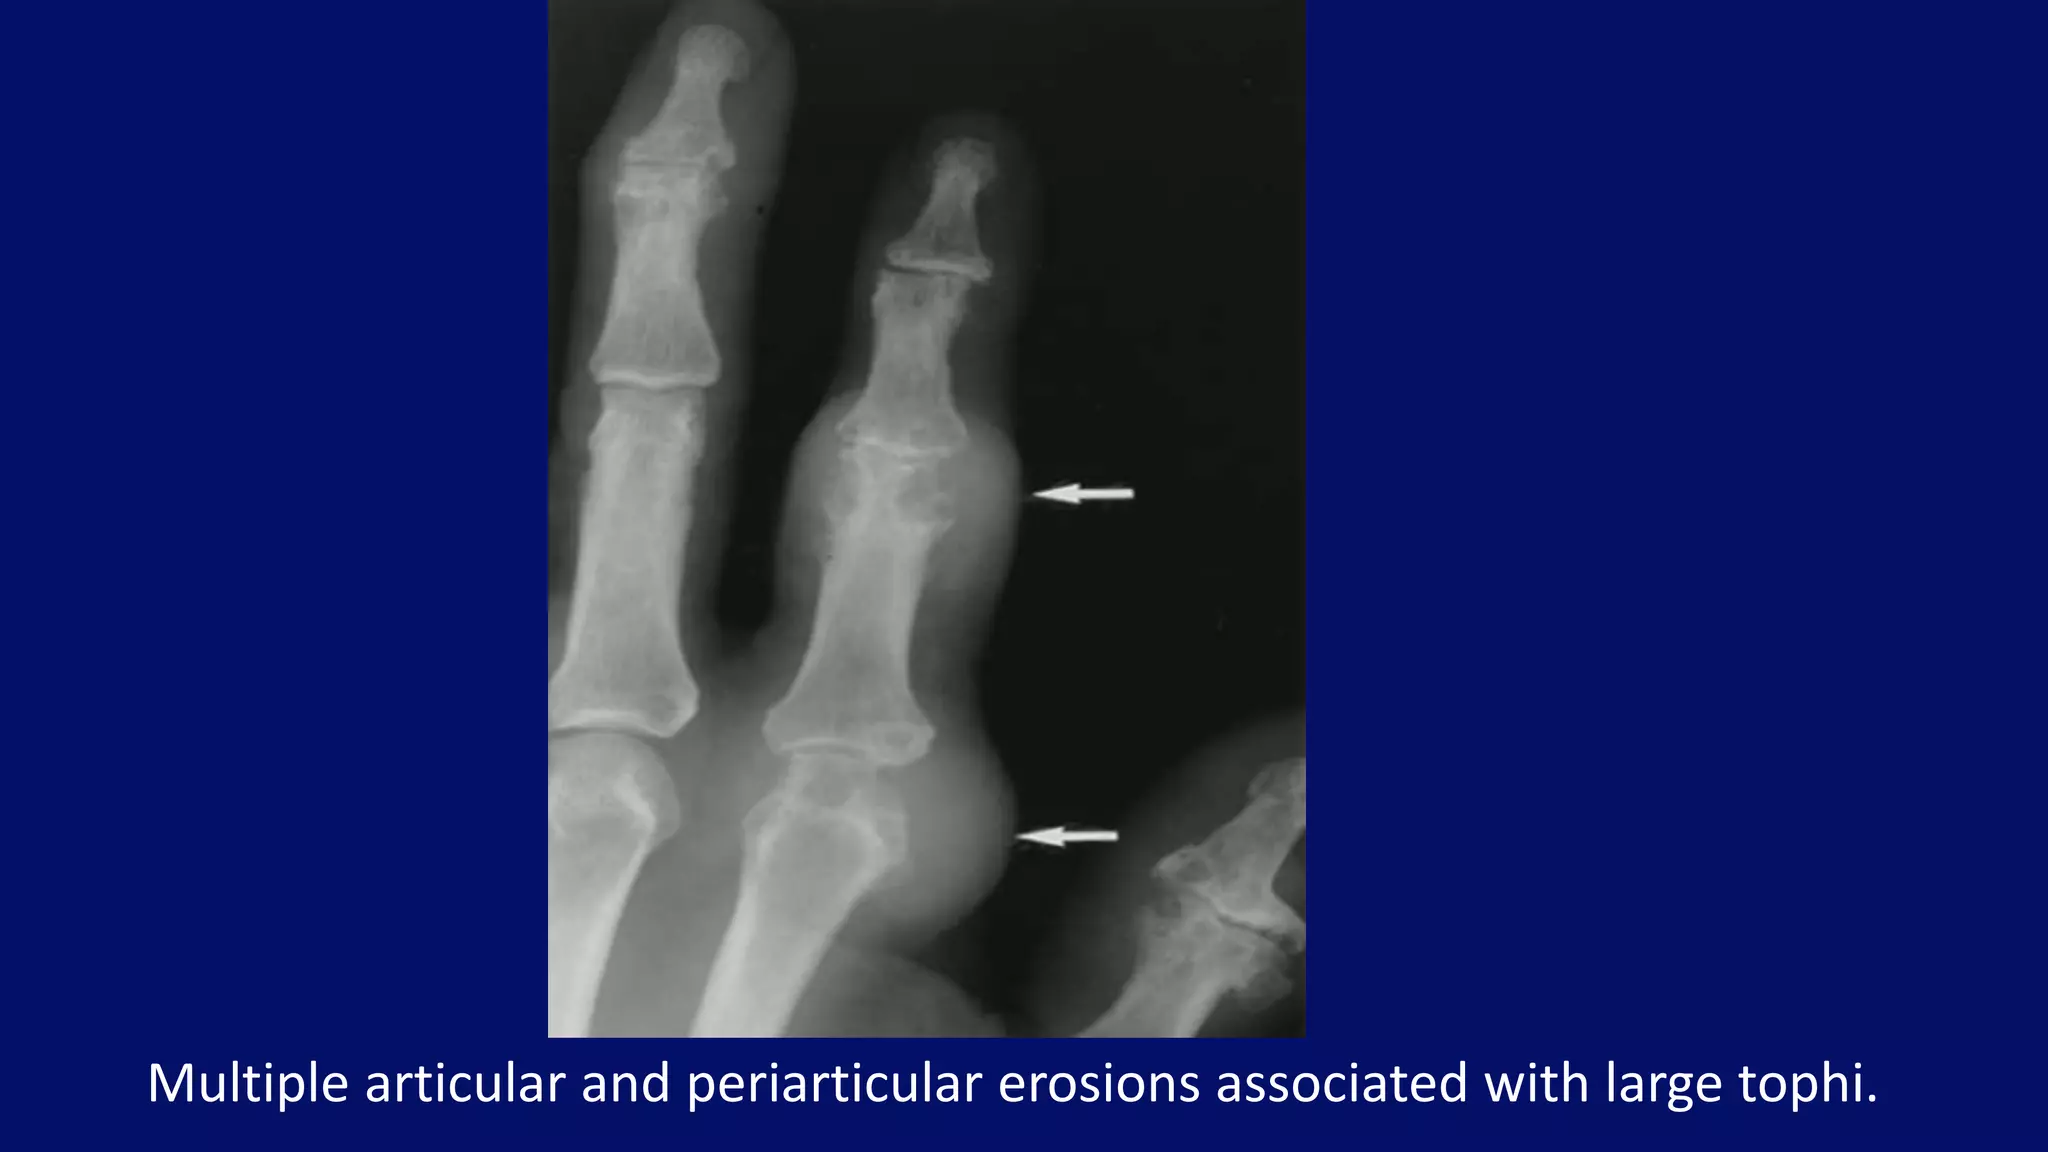

Multiple articular and periarticular erosions associated with large tophi.

Prominent osteophytes

Vacuum disc